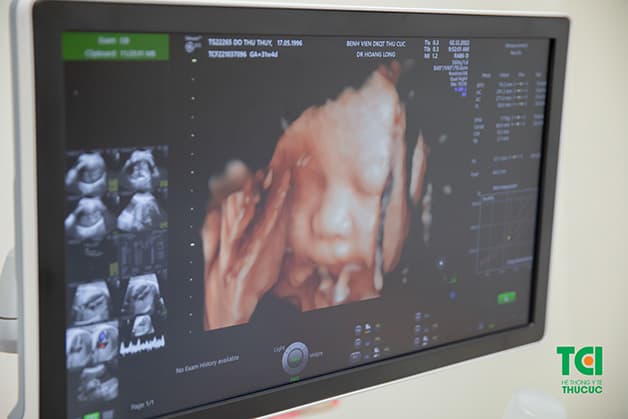

Khám thai tuần 32 khám những gì? Khi đi khám thai tuần 32, thai phụ sẽ được khám thai lâm sàng để kiểm tra các chỉ số như cân nặng, huyết áp, tim, phổi; thăm khám cận lâm sàng gồm siêu âm màu 4D để kiểm tra hình thái thai nhi; xét nghiệm nước tiểu với 10 thông số; xét nghiệm máu…

Trong lần khám thai này, thai phụ sẽ được siêu âm “chốt” trước sinh để phát hiện một số vấn đề về hình thái thai nhi xảy ra muộn, như: Bất thường ở tim, mạch, cấu trúc não… Mặc dù các dị tật được phát hiện ở thời điểm này không thể can thiệp song nó giúp sản phụ và người nhà ứng phó bằng cách lựa chọn nơi sinh, phương pháp sinh phù hợp, chuẩn bị về chăm sóc, khám chữa cho trẻ ngay sau khi sinh.